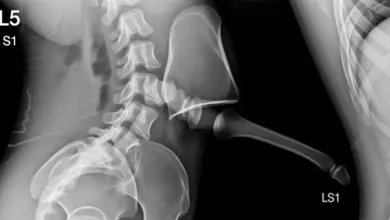

Sacralização de L5: sintomas, diagnóstico e tratamento

A sacralização de L5 é uma variação anatômica em que a quinta vértebra lombar se funde parcial ou totalmente ao…

L5-S1: tudo sobre a articulação lombossacra

A articulação L5-S1 é o ponto de transição entre a coluna lombar e o sacro. Essa região suporta altas cargas,…